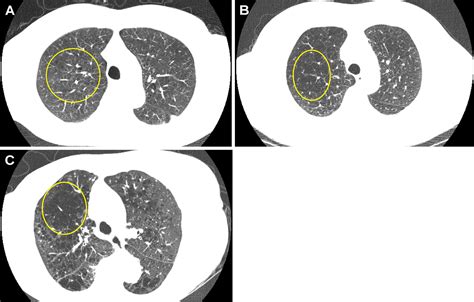

• Chest X-rays and CT Scans: Used to visualize the structure of the lungs. They can show the enlarged air spaces typical of emphysema or identify suspicious nodules or masses that might indicate cancer.